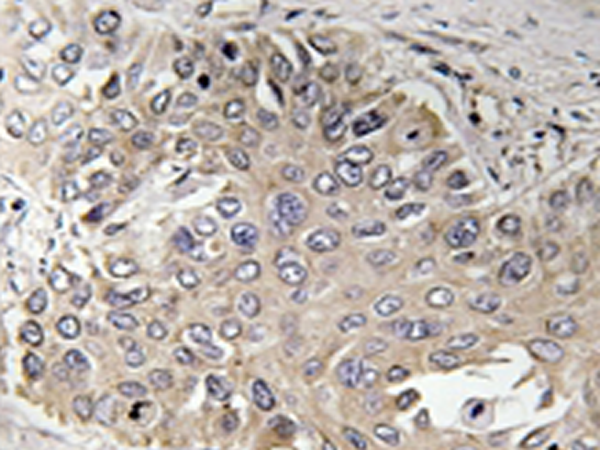

IHC positive control: |

Human lung carcinoma tissue |